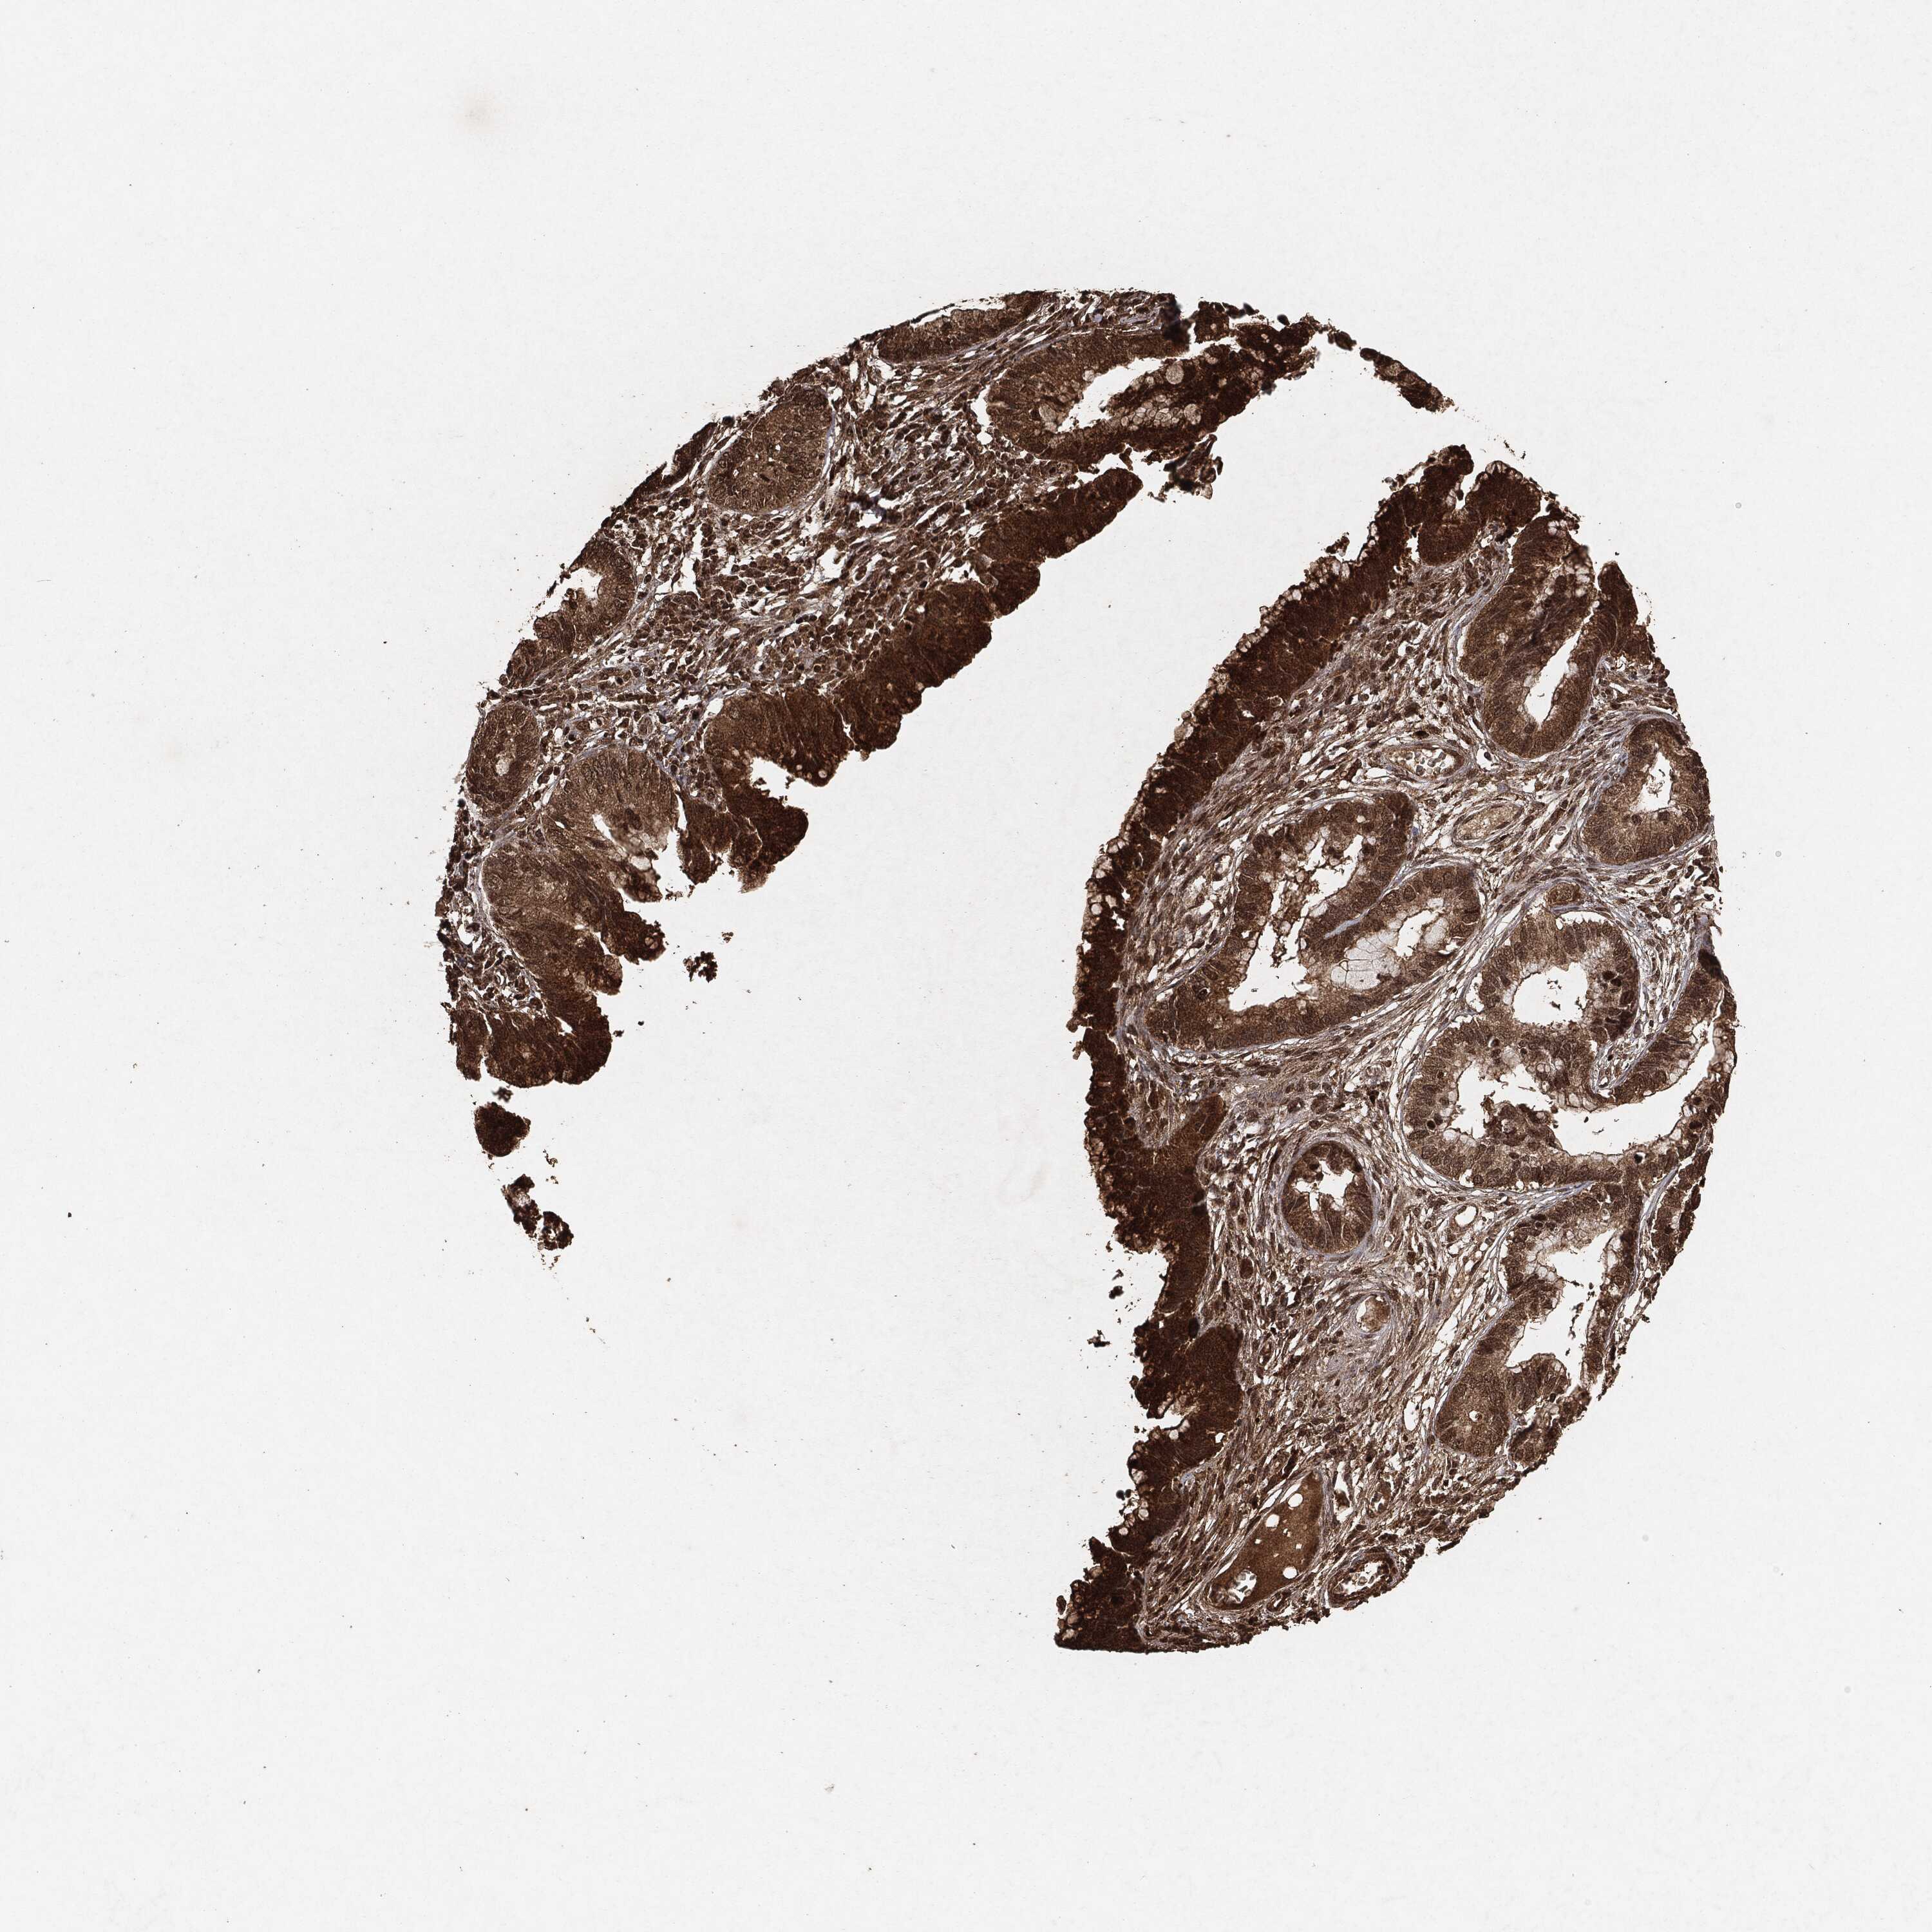

CERVICAL CANCER - Protein expressioni

A mouse-over function shows sample information and annotation data. Click on an image to view it in a full screen mode. Samples can be filtered based on level of antibody staining by selecting one or several of the following categories: high, medium, low and not detected. The assay and annotation is described here.

Note that samples used for immunohistochemistry by the Human Protein Atlas do not correspond to samples in the TCGA dataset.

Antibody stainingi

Antibody staining in the annotated cell types in the current human tissue is reported as not detected, low, medium, or high, based on conventional immunohistochemistry profiling in selected tissues. This score is based on the combination of the staining intensity and fraction of stained cells.

Each image is clickable and will lead to virtual microscopy that enables deeper exploration of all samples and also displays staining intensity scores, fraction scores and subcellular localization as well as patient and tissue information for each sample.

HPA001200

HPA018530

CAB000035

CAB068186

CAB073534

CAB080313

CAB080314

CAB080473

CAB080475

CAB080506

CAB080507

CAB080509

CAB080510

CAB080511

Staining

High

Medium

Low

Not detected

Intensity

Strong

Moderate

Weak

Negative

Quantity

>75%

75%-25%

<25%

None

Location

Nuclear

Cytoplasmic/membranous

Cytoplasmic/membranous,nuclear

Adenocarcinoma, NOS

Squamous cell carcinoma, NOS